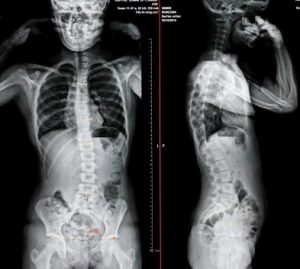

Scoliosis is an abnormal curvature of the spine, which is most likely to affect young children and young people. According to the research of the Chiropractic Department, it is usually caused by the imbalanced growth of the spine and muscles, or the abnormal growth of the spine and nerves, and some scoliosis is caused by virus infection, whether it is congenital or acquired, the reasons for its occurrence are still under investigation. Regardless of the cause, the most important thing is to be able to detect the spine and arrange  treatment as soon as possible. If the parents or doctors can detect the abnormal growth of the spine of the child as soon as possible, and arrange a course of treatment according to their needs to correct the abnormal curvature, or prevent the curvature from deteriorate, this is the most practical way.

(1) Is the spine flat and aligned with the bones?

(2) Are the left and right sides of the head, shoulders, and pelvis balanced?

(3) Whether the shoulder blades are balanced and whether the two shoulder blades are at the same alignment.

(4) Are the ribs balanced on both sides?

(5) Are both spinal muscles balanced?